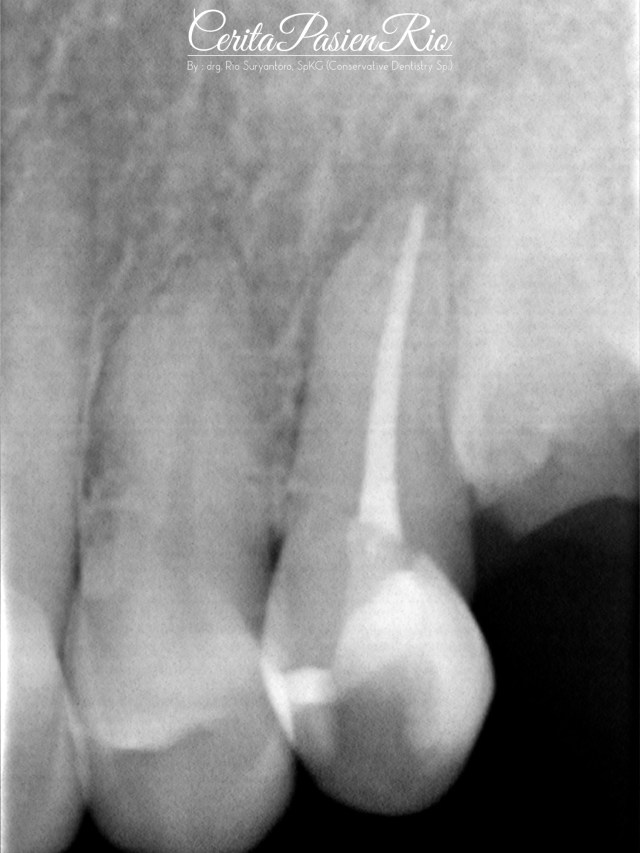

Gambar 27. evaluasi radiograf dengan foto xray dental yang dilakukan pasca penambalan. tampak integritas tepi resin komposit yang rapat dan homogenitas dari restorasinya yang padat.